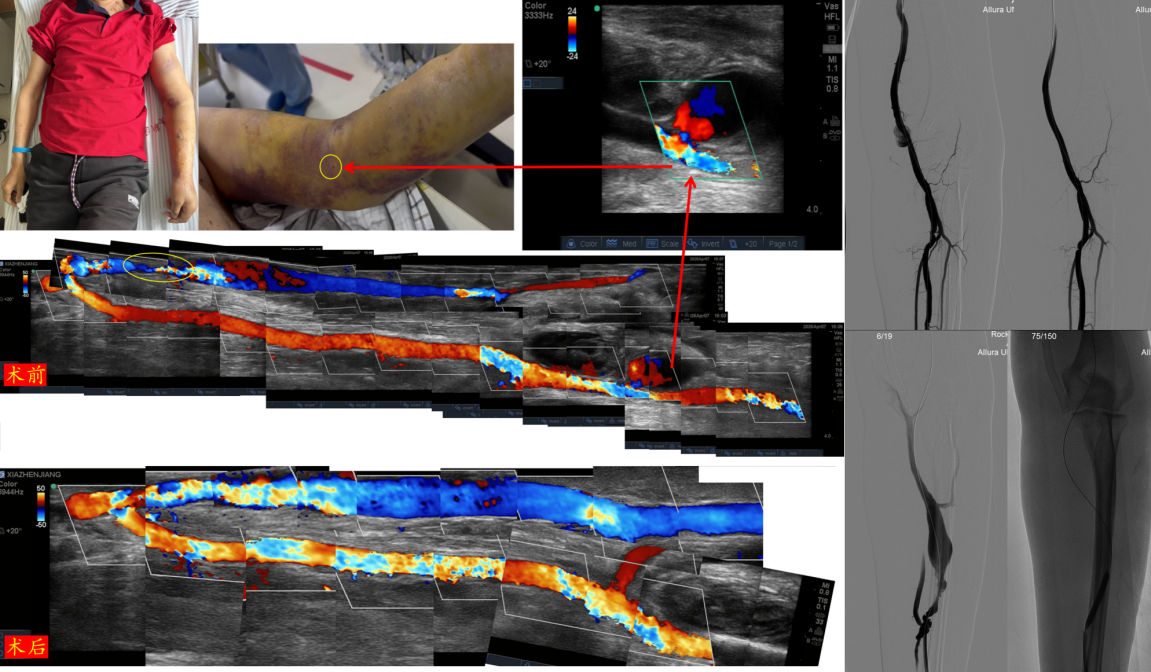

张先生依靠左上肢动静脉内瘘血液透析治疗3年多,4天前突发左上肢剧烈胀痛,当时未予重视,后胀痛加重伴广泛淤青无法穿刺进行血液透析治疗,伴左上臂无法抬起、不能握拳。我院血管通路团队经仔细的查体和超声等评估,发现在张先生左肘部肱动脉上有一个4mm“洞”口一直在出血,已形成假性动脉瘤及皮下巨大血肿,同时发现左前臂动静脉内瘘有长段重度狭窄。

血管通路团队对张先生的病情进行细致分析,考虑到患者高龄、基础疾病多,传统开放手术创伤大、恢复慢,团队与家属充分沟通方案利弊,快速制定出个体化的分步精准救治方案。血管通路团队在动静脉内瘘吻合口入路,仅用一个针眼,通过“覆膜支架置入术+动静脉内瘘狭窄球囊扩张术”同时封堵了动脉的破口及扩张了狭窄内瘘,一举两得。

术后第二天,张先生左上肢肿胀及疼痛症状明显改善,内瘘震颤恢复正常,透析通路功能良好,平稳出院。作为慕名而来的外地患者,张先生及家属对医院肾内科快速的救治应急、周密的术前准备、精湛的微创技术、全程细致的诊疗服务深表感谢。